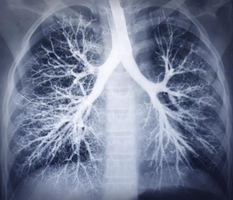

Interventional pulmonology is a field within pulmonary medicine that focuses on the use of advanced techniques and technology to diagnose and treat patients with lung diseases such as asthma, COPD and lung cancer.

Other pulmonary interventions include:

- Bronchoscopy - diagnosis and treatment of lung problems using a long, thin tube – called a bronchoscope – inserted through the nose or mouth and into the airways.

- Endobronchial ultrasound (EBUS) - a bronchoscopic procedure used to obtain images of and extract fluids from the lungs and lymph nodes for the purpose of biopsy.

- Navigation bronchoscopy – used to locate hard-to-find tumors and control bleeding in the airways.

- Radial probe – an ultrasound probe used to provide real-time images to localize tumors.

- Needle biopsy – A needle is used to extract fluid from the lung.

- Transbronchial biopsy – A bronchoscope is used to move a tiny camera into the main airways of the lungs.

- Cryobiopsy – Lung tissue sticks to a frozen probe, which is inserted and extracted through a bronchoscope.

- Thoracentesis – Fluid is extracted from the area between the lungs and the chest wall.

- PleurX catheter – a tube inserted in the chest cavity to drain excessive fluid around the lungs.

- Percutaneous tracheotomy – a minimally invasive procedure to allow the patient to breathe when the nose and mouth are obstructed.

- Pulmonary function testing – a series of tests used to determine how well your lungs are working.